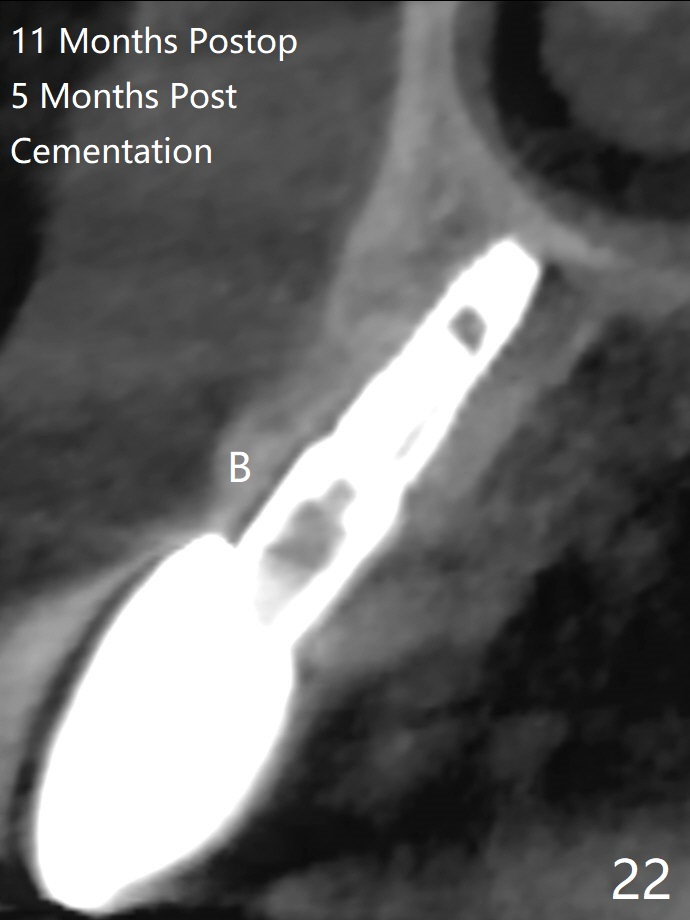

A 62-year-old man with generalized chronic periodontitis returns with chief complaint of loose tooth at #11 (Fig.1). Although a buccal fistula (Fig.1 <) is closer to #12 than to #11, percussion is more severe at #11 than 12. The buccal plate of #11 is missing, but it is possible to place a narrow immediate implant because of the wide alveolus (Fig.2). Since the gingiva is ~ 10 mm long, a mill abutment is to be used (Fig.3,5). In fact the fistula communicates with #11 extraction socket. After debridement, osteotomy is initiated (Fig.4) for a 3.8x10 mm implant ~ 35 Ncm, followed by seating a 4.5x2 mm mill abutment (Fig.5). Abundant sticky bone is placed in the remaining socket (for buccal plate reconstruction) and against the root surface of the neighboring teeth (Fig. 6 * (#10,12)). Finally 2 pieces of PRF membranes are utilized to facilitate repair of the buccal soft tissue defect (Fig.7 *). The root prominence of the canine seems to be maintained by the bone graft (Fig.8 C). Acrylic dressing holding the PRF membranes in place remains in situ with the healthy gingiva buccal (Fig.9) and palatal (Fig.10) 11 days postop. Note the acrylic locking into the undercuts of the neighboring teeth (*). 经过一段摸索发现离心每分钟1500转5分钟后,抽取上清液,接着再离心10分钟剩余上清液就形成血小板块,压制后便是血小板膜,后者似乎有助于软组织愈合,而上清液用来制备骨块,帮助硬组织生长。利用这个原则讨论以下病例治疗。The gingival margin gains ~ 5 mm 6 weeks postop when the acrylic dressing is removed (Fig.11,12 (<: previous one), as compared to Fig.7,8). 治疗结束时尖牙牙龈缘高于第一双尖牙(图七,八),六个星期后,尖牙牙龈缘却低于双尖牙(图十一,十二(箭头:原始牙龈缘))。术后2.5,4.5月基台周围牙龈似乎能与钛合金附着,防止细菌进入深部植体(图十三,十四)。临时牙冠脱落多次,可能与mill abutment太光滑有关,所以颊侧,舌侧磨成平面(图十四)。取模时好像不必取出基台清洗(仿佛没有炎症),原位用树脂延长基台。术后5个月CT显示颊侧骨板再生(图十六-十八)。取模时并没有用树脂加长基台;粘固时,牙冠颜色理想,但是照片中并不是如此(图十九,二十),颊侧骨板没有塌陷。术后11个月基台颊侧骨板没有萎缩(图二十一:B);3d图像:骨壁完全形成(图十六对比:部分形成)。密度也增高(图二十二:B),与术后五个月比较(图十七)。术后十一个月,粘固后五个月角化龈存在(图二十三),牙冠颈部有金属颜色透出,是因为二段式基台太粗了(最细4.5毫米),可以请实验室在牙冠内部涂opaque material而减轻。